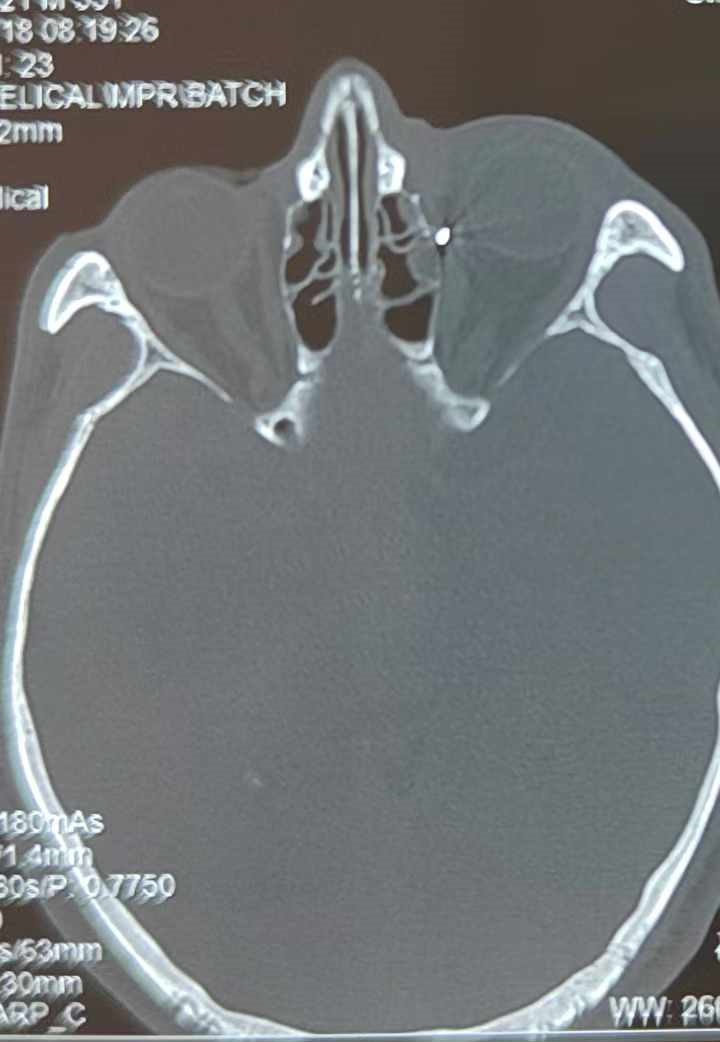

裝修工人高先生在作業(yè)過(guò)程中不慎被砸傷左眼,送至廈門(mén)眼科中心救治時(shí),眼外傷及眼底病2科副主任醫(yī)師李海波博士在CT檢查報(bào)告中發(fā)現(xiàn),進(jìn)入眼內(nèi)的異物在眶尖極為隱匿的位置,想要“不動(dòng)聲色”地取出來(lái),有些難度。

從CT報(bào)告中可以看出,高先生眼內(nèi)的異物不是很大,但位于眼窩深處,緊鄰鼻骨,從CT影像判斷應(yīng)該是金屬或合金異物。一般臨床上遇到這樣的情況,醫(yī)生會(huì)建議“保守觀察”,若異物傷及神經(jīng)、發(fā)生炎癥感染等,則需到條件較好、有眼眶病和眼外傷專(zhuān)業(yè)醫(yī)師的醫(yī)院進(jìn)行二期眶內(nèi)異物取出術(shù)(2021年《中國(guó)眼眶異物診斷和治療專(zhuān)家共識(shí)》)。

李海波博士介紹,眶內(nèi)異物想要通過(guò)手術(shù)取出,難度很大,一是因?yàn)槲恢秒[匿,無(wú)法實(shí)現(xiàn)可視化操作;二是如果是磁性異物,現(xiàn)有手術(shù)工具磁性強(qiáng)度有限,很難吸出這么深的異物;三是可操作空間極為狹小,眶周軟組織多,異物周邊包裹緊密,像高先生這種情況,異物周邊還有很多神經(jīng)、血管,手術(shù)難度更高。

手術(shù)十分順利,李海波博士設(shè)計(jì)好了取出路徑,用這根細(xì)磁棒取出了一個(gè)米粒大小的鐵屑,過(guò)程中未造成二次傷害和大創(chuàng)面?zhèn)?。術(shù)后CT檢查顯示,高先生眼內(nèi)再無(wú)異物,他此時(shí)才松了一口氣。